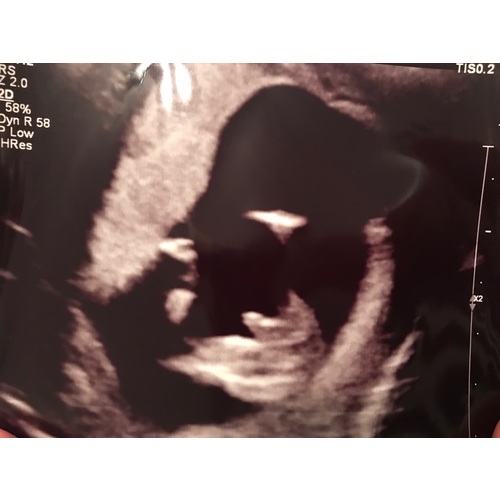

Bij ons werd uitgelegd dat wanneer de streepjes naar binnen gaan t een meisje is, en als je een uitstulping ziet het een jongen is.. lijkt mij op deze echo heel duidelijk een meisje !

een meid denk ik hoor, je ziet echt 2 strepen zo was het bij alle 3 mijn meiden. gefeliciteerd!

Ik denk dat het inderdaad een meisje is.